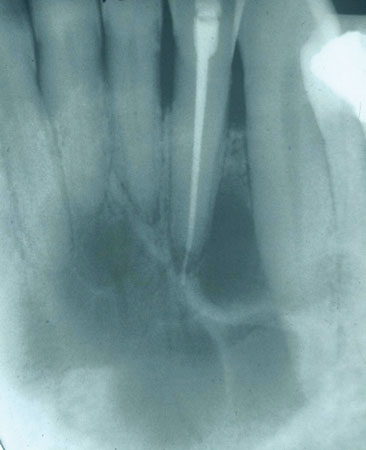

Figure 2

Significant microscopic characteristics: CGCG is noted for the many multinucleated giant cells that are found within the tissue specimen. The multinucleated giant cells are within a sea of spindle-shaped mesenchymal cells and found in areas of hemorrhage.

The giant cells may vary in size and number with scattered placement, or they may be concentrated within distinct areas of the specimen. Newly formed bone may be present within the specimen as well. The more aggressive type of CGCG is not distinguishable from the nonaggressive type by microscopic examination (see Figure 2).